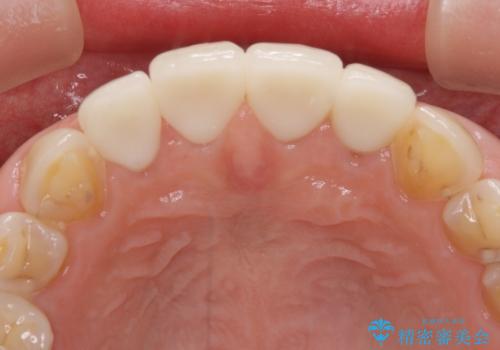

- 咬み合わせと度重なる応急処置の繰り返しにより、前歯がガタガタになってしまったとのことで来院された患者様です。

4本の前歯が気になっていたので、全てをオールセラミッククラウンにて補綴治療を行うこととしました。

口元への目線ばかりを気にしていた状態から、自然な口元へと変貌し、患者様には大変満足していただきました。